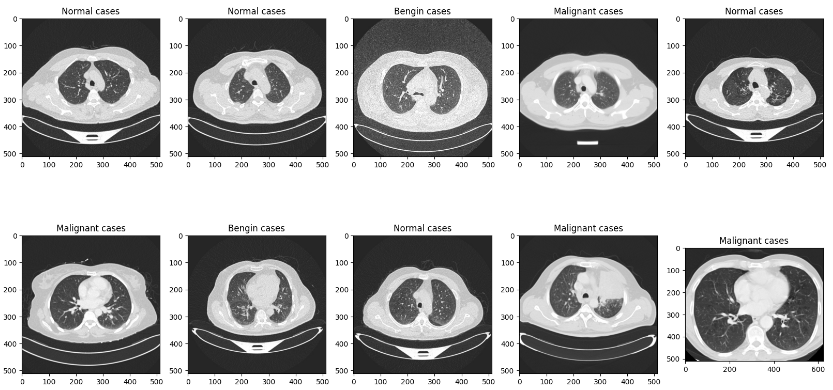

plt.figure(figsize=(20, 10))

for i in range(10):

test_img_path = os.path.join(test_root, test_file_list[i])

ori_img = Image.open(test_img_path).convert('RGB')

plt.subplot(2, 5, (i+1))

plt.title(test_file_list[i].split('/')[-2])

plt.imshow(ori_img)

plt.show()